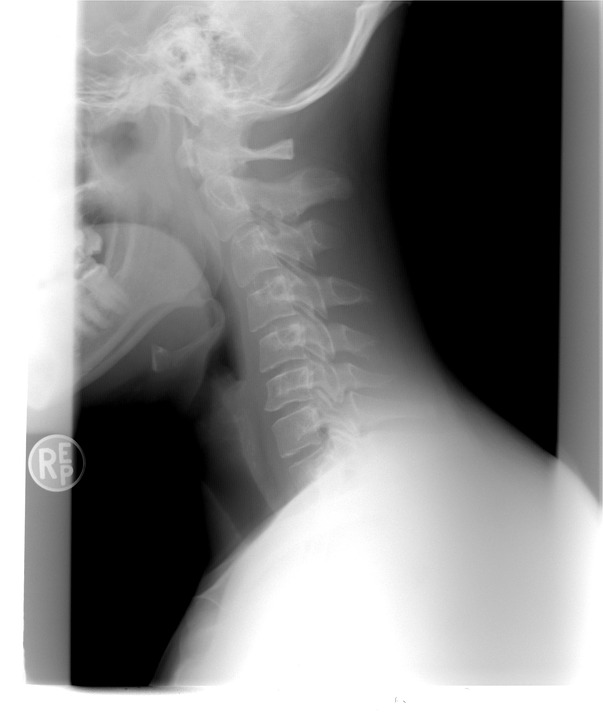

吉姆到院後醫生為他檢查,發現他靠近頭骨的兩個椎骨骨折了,並馬上為他治療。吉姆說,雖然為了戴上輔助器,吉姆的頭骨上鑽了4個洞,且每兩個禮拜必須回到醫院檢查,但他相當感激,「可以確定的是,我是個幸運的傢伙,醫生說我可以完全復原」。

▼吉姆摔斷了頸椎。(示意圖/翻攝自Pixabay